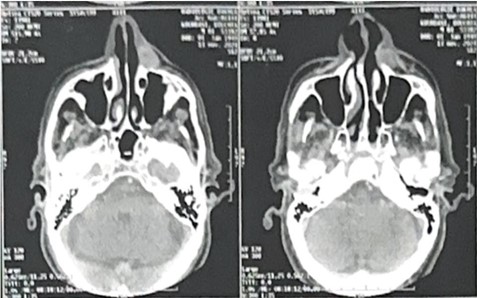

A maxillofacial CT scan was performed (Figure 3), revealing a lesion in the left nasogenian sulcus measuring 21.6 × 26 × 12.7 mm. It was in contact with the nasal bone and maxilla without any evidence of bony erosion. A second lesion was also identified in the right nasogenian sulcus, located anterior to the right masticator space and external paramaxillary region. This lesion was ovoid, well-defined, and measured 20 × 23 × 27 mm, with no evidence of infiltration or cutaneous thickening.

Figure 3: Axial facial CT scan showing the location of the mass in relation to the nasolabial fold.

Radiologically, PA appears as a well-defined, homogenous soft-tissue mass. On CT scans, it typically shows a non-invasive, rounded lesion without bone erosion or calcifications. MRI, which was not used in this case but is considered superior for soft tissue characterization, usually shows a lesion with low-to-intermediate signal intensity on T1-weighted images and high intensity on T2-weighted images, often with a well-defined capsule [6,7]. In our patient, the CT showed regular, ovoid lesions without bony destruction or signs of deep invasion, which supported a benign etiology.